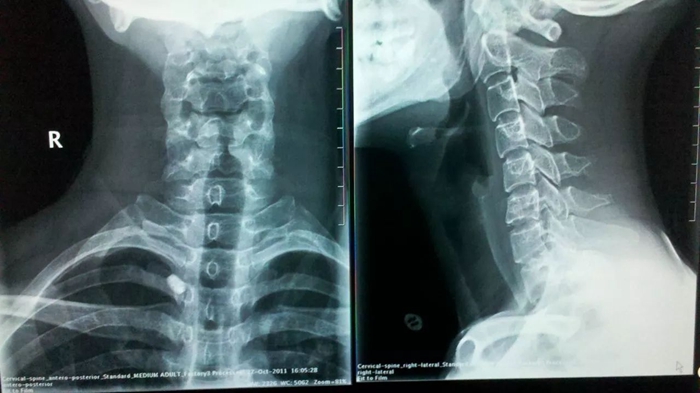

一般判定主要是通过医生问诊配合X光拍照、CT等影像学检查手段进行判定,首先通过问诊确认患者是否存在颈椎病的临床表现(肩颈背部疼痛、头痛头晕、手臂痛麻、活动受限等),再结合X光片等判断颈椎间盘是否有变性、膨隆、突出征象,邻近骨关节及软组织是否有软骨退化、骨质增生、韧带钙化、颈椎不稳等退行性改变。